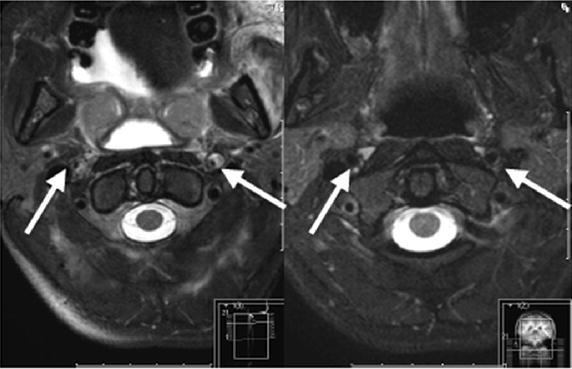

We report on a 28-year-old female major trauma patient (injury severity score, ISS 50) who was involved in a motor vehicle accident. She was primarily transferred to a level II trauma center. After initial assessment and operative management, an anisocoria was diagnosed on the intensive care unit. Subsequent CT angiography and extracranial duplex sonography revealed a bilateral internal carotid artery dissection. The patient was transferred to our level I trauma center where conservative treatment with high-dose heparin therapy was started at day two after trauma. Outcome after 6 months was very good.

我们报告一名28岁女性严重创伤患者(损伤严重度评分,ISS 50),她遭遇了机动车事故。她最初被转至二级创伤中心。经过初步评估和手术处理后,在重症监护病房诊断出瞳孔不等大。随后的CT血管造影和颅外双功超声检查显示双侧颈内动脉夹层。患者被转至我们的一级创伤中心,于创伤后第二天开始采用大剂量肝素治疗进行保守治疗。6个月后的结果非常好。